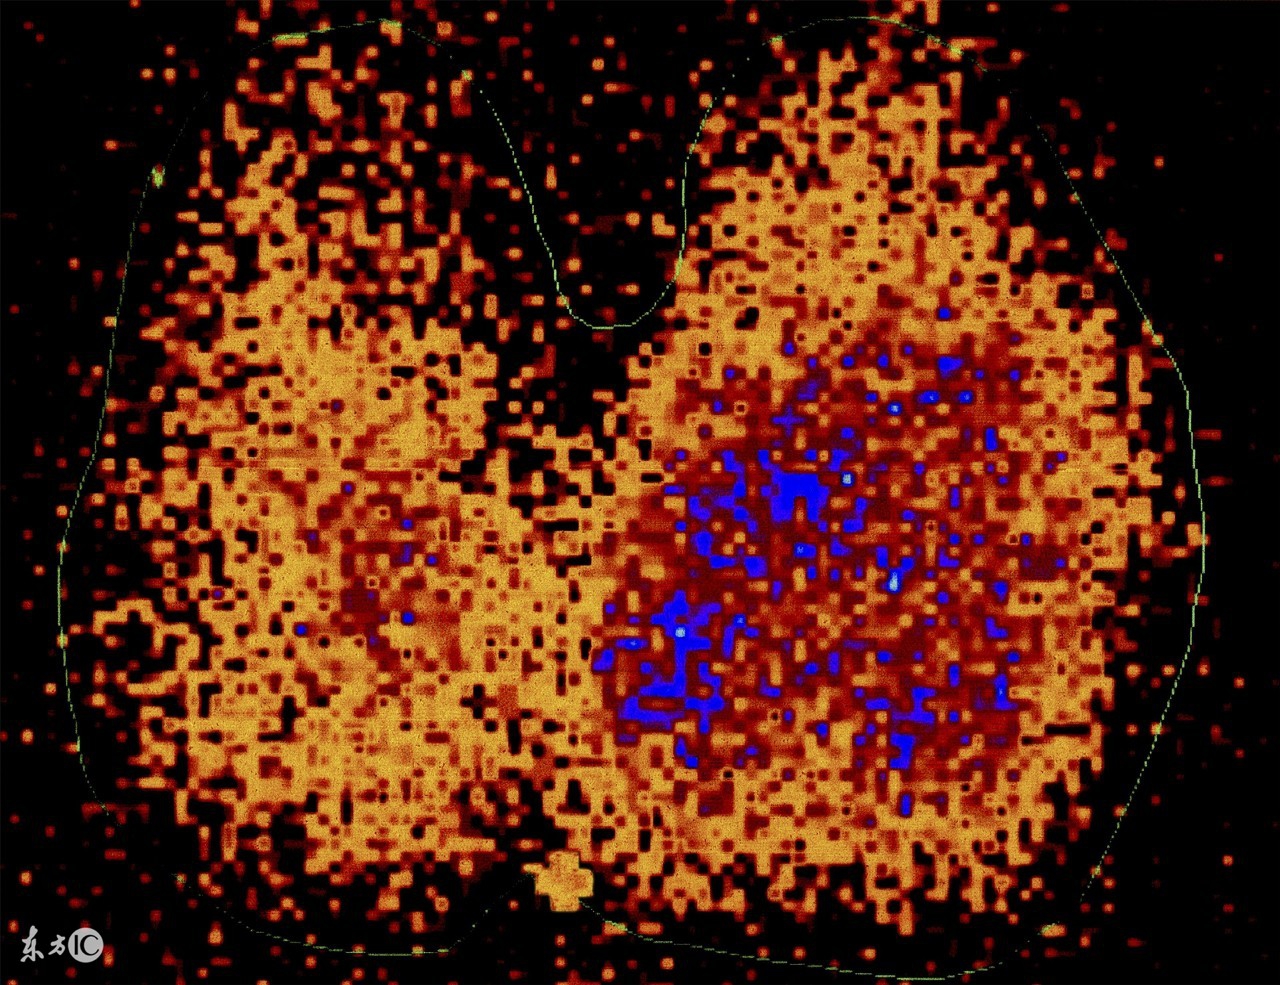

1 、 目的 :通过控制食物中碘的摄入量、辅助同位素甲状腺功能检查。

2 、 适应证 :甲状腺功能检查。